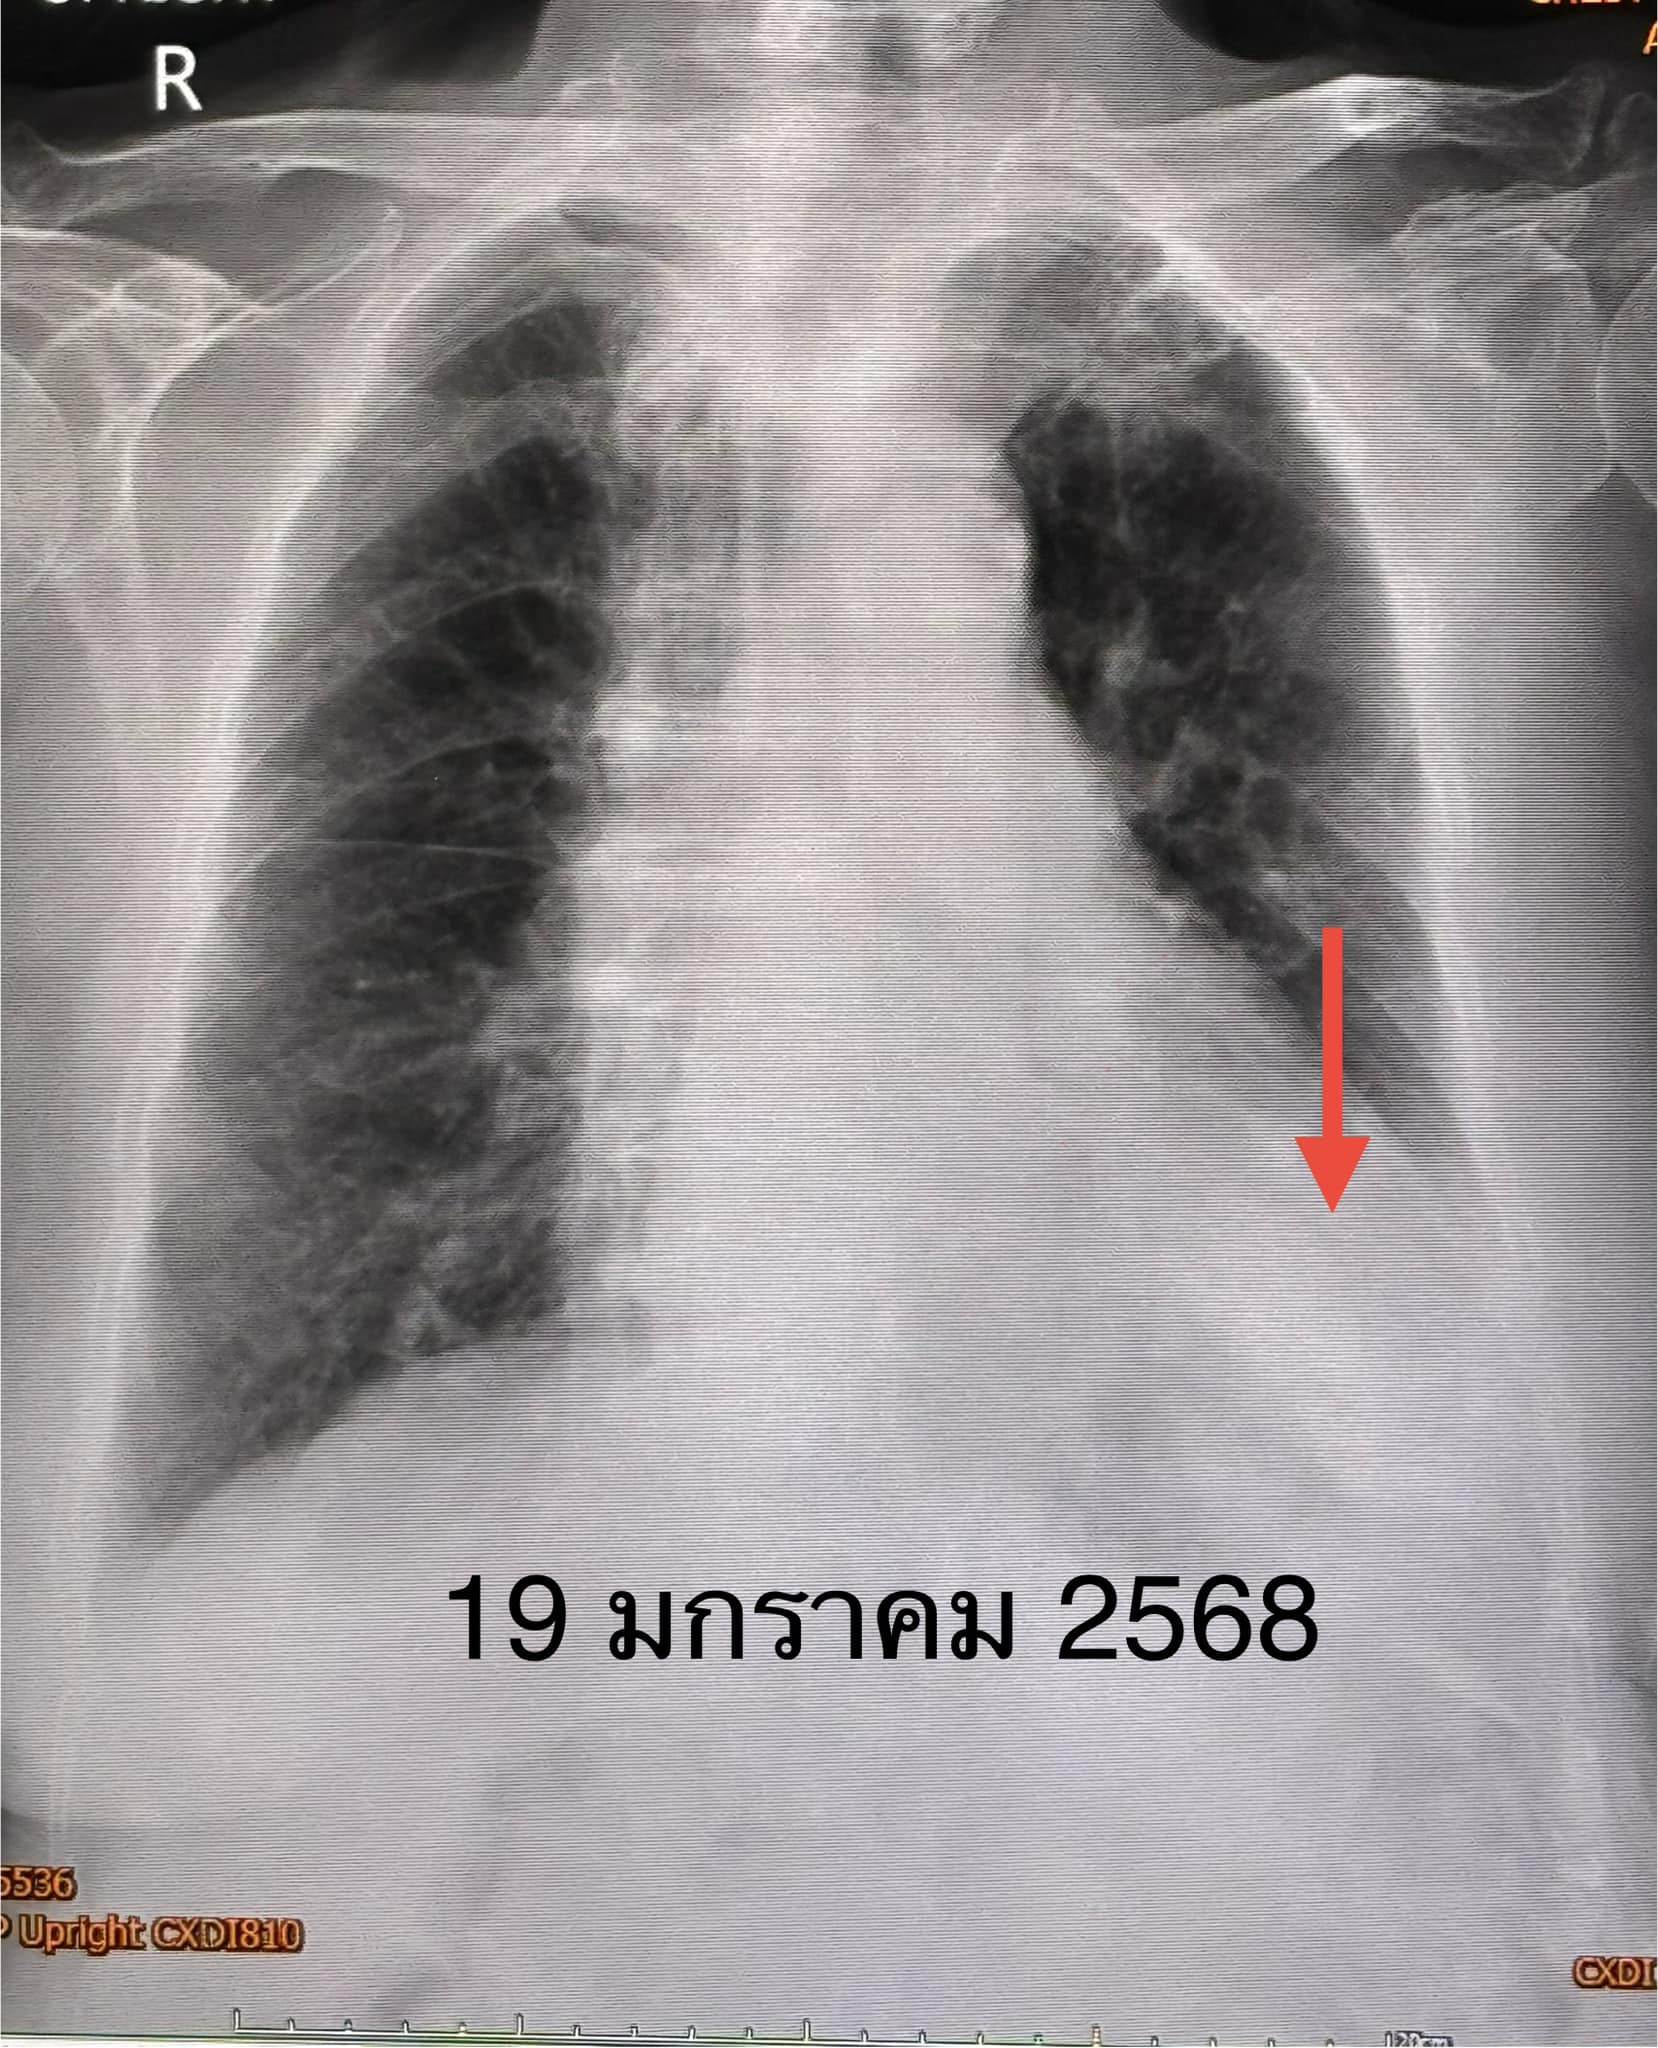

“2 วันต่อมาเริ่มมีไข้ ไอตอนแรกมีเสมหะใสๆ ต่อมาเสมหะมากขึ้น เหนื่อย ไม่มีน้ำมูก ไม่เจ็บคอ ไม่ปวดหัว ไม่ปวดตัว เข้าไปนอนรักษาในโรงพยาบาลแถวปากช่อง เอกซเรย์ปอดที่นั่น พบผิดปกติข้างซ้ายด้านล่าง ส่งเสมหะย้อมไม่พบเชื้อวัณโรค หรือแบคทีเรีย ส่งเลือดเพาะเชื้อไม่ขึ้น ได้ยาปฏิชีวนะ ยังไม่ดีขึ้น ขอย้ายรพ. เมื่อวันที่ 19 มกราคม 2568”

“ตรวจร่างกาย ระดับออกซิเจนที่ปลายนิ้วต่ำ 87% ต้องให้ออกซิเจน 2 ลิตร/นาที ไม่มีไข้ ฟังปอดมีเสียงผิดปกติเล็กน้อยที่ปอดข้างซ้ายด้านล่าง เจาะเลือด เม็ดเลือดขาวในเลือดปกติ เอกซเรย์ปอดมีฝ้าขาวในปอดข้างซ้ายด้านล่าง (ดูรูป) ทำคอมพิวเตอร์ปอดยืนยันว่ามีฝ้าในปอดข้างซ้ายด้านล่าง และมีน้ำในช่องเยื่อหุ้มปอดเล็กน้อย (ดูรูป) ตรวจเลือดเม็ดเลือดขาวปกติ แยงจมูกส่งตรวจรหัสพันธุกรรมเชื้อ 22 สายพันธุ์ไม่พบเชื้อ ส่งเลือดตรวจ Legionella pneumophila Antibody IgM positive 1:200”

“วินิจฉัย: ติดเชื้อแบคทีเรียลีจิโอเนลลา นิวโมฟิลา Legionella pneumophila ทำให้ปอดอักเสบ ให้ยา azithromycin และ levofloxacin คนไข้ดีขึ้น ไม่ไอ ไม่เหนื่อย ระดับออกซิเจนปกติ ไม่ต้องใช้ออกซิเจน วันที่ 26 มกราคมเอกซเรย์ปอดกลับมาเป็นปกติ (ดูรูป)”